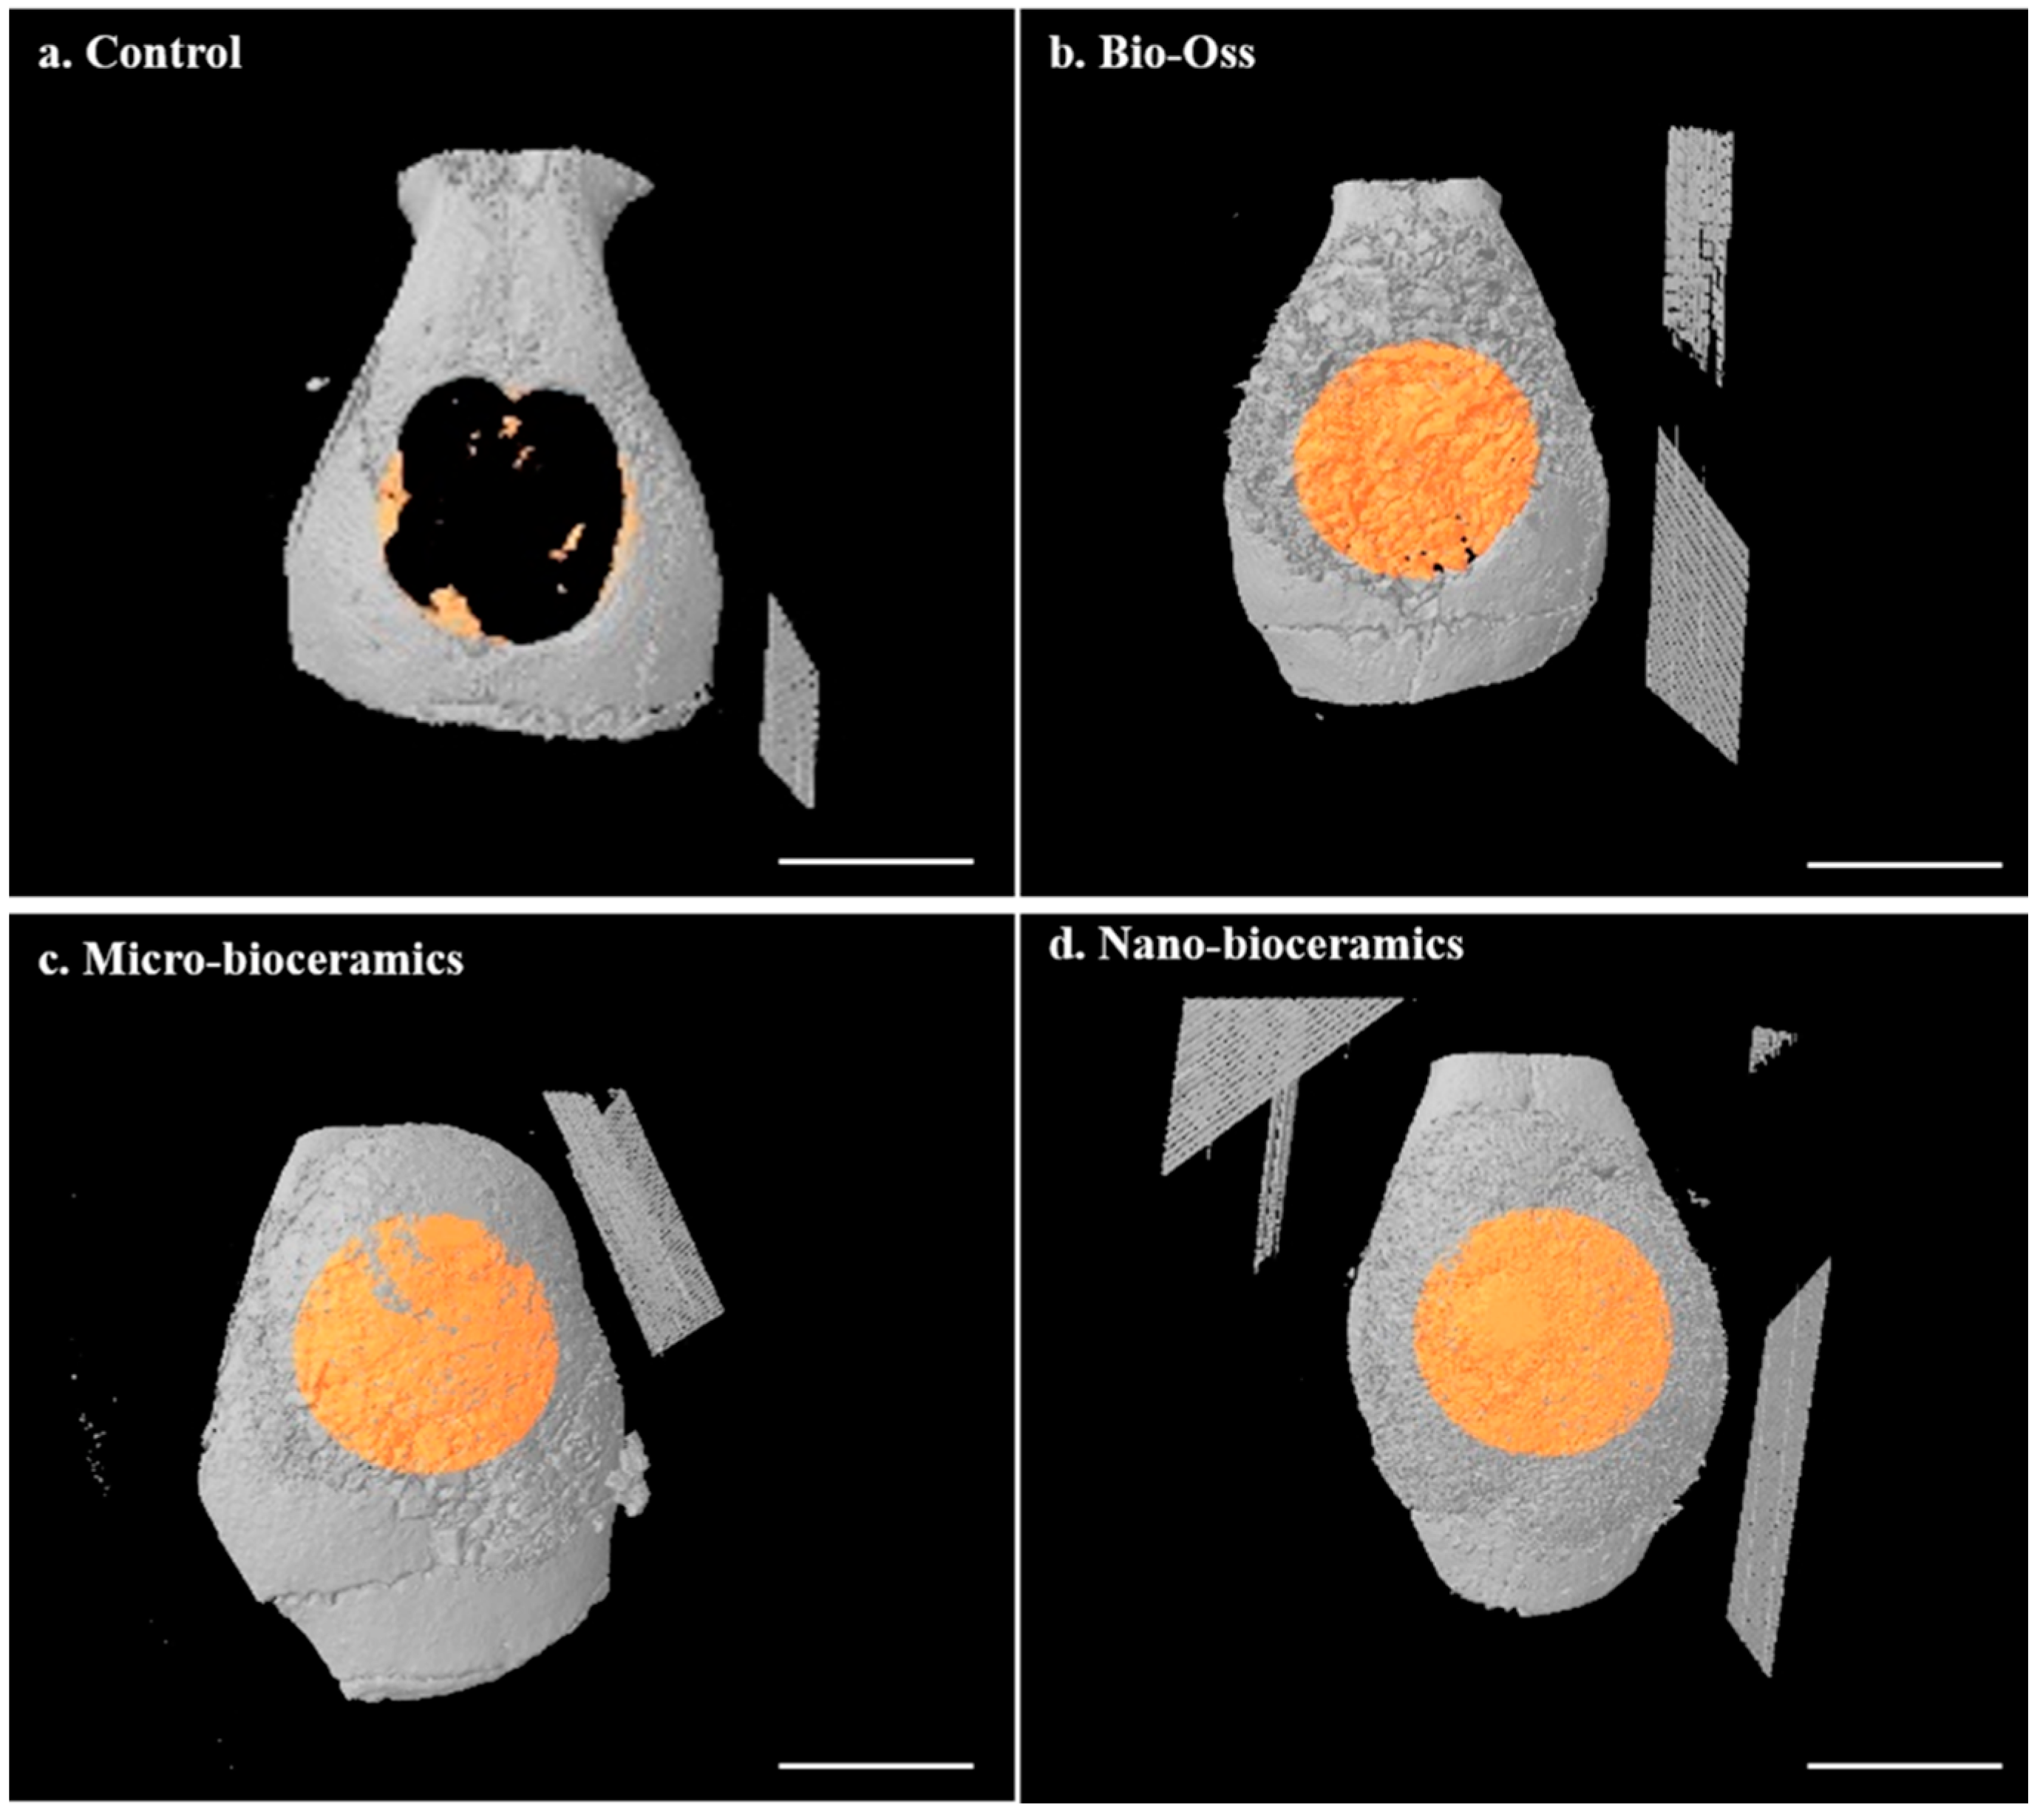

2.7. Micro-Computed Tomography (µCT) Analysis